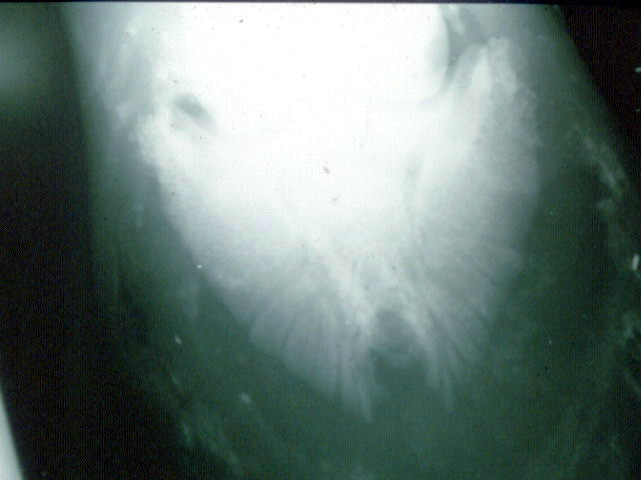

abcès qui a duré 7 mois et demi, Boiterie typique abcès qui s'atténue en une semaine, on passe par tous les diagnostiques possibles, faute d'examen radiographique, la jument est mise au parc. Ce sera une déformation de la paroi en pince qui va pousser le client à faire une radio (à l'époque pas de radio mobile).

Une fois l'abcès enkysté enlevé, la jument n'a plus boité.

un cas d'ostéomyélite, pronostic sombre, au vu de la photo...

Voici les photos retrouvées datant de 2012...

Superbe abcès du postérieur, sortie en pince après grattage. L'ampleur de la galerie faite sous la sole est assez belle. Ensuite toute la sole avait sauté.